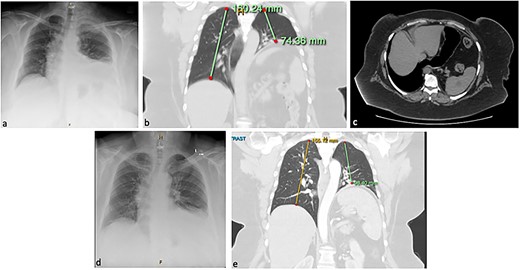

One year prior to our consultation, the patient had sustained a workplace injury leading to C5/C6 disc damage and left thoracic outlet syndrome. She had trialled medical therapy to resolve neurogenic symptoms before proceeding to surgical intervention involving internal fixation of her lower cervical spine, left first rib resection, and scalenectomy with brachial plexus neurolysis. In Day 1 postoperative chest X-ray (CXR) showed an elevated left hemidiaphragm (Fig. 1a) that was persistent on computed tomography (CT) imaging 1 month later (Fig. 1b; see Video 1), along with complete left basal collapse and lingular atelectasis. This suggested paralysis of the left hemidiaphragm, likely due to a left phrenic nerve injury, with a resulting loss of 60% of lung volume and displacement of the mediastinal structures to the right. The patient had a trial of conservative management. However, increasing reflux and dyspnoea symptoms warranted gastroscopy and volumetric CT that showed an acute angularis angulation of the sleeve (Fig. 1c) and a large gastric volume of 495 ml, in addition to an ongoing high-riding diaphragm on the left side.

Chest X-ray (CXR; a) and computed tomography (CT) of the chest and abdomen in coronal (b) and axial (c) planes, showing eventration of the left hemidiaphragm and angulation of the stomach. Resolution of eventration on CXR at one day post-plication on CXR (d) and on CT at six months post-plication (e).

In Day 1 postoperative CXR showed a normal-riding left diaphragm (Fig. 1d). The patient was discharged home on postoperative Day 3, following an unremarkable and satisfactory recovery. At 6-week follow-up, she was tolerating a normal diet, had no respiratory symptoms or reflux, and had reduced her weight to 128 kg. Six months postoperatively, she remained free of respiratory symptoms and was tolerating a diet. Her weight remained stable. She underwent a gastroscopy that showed that the hiatus hernia repair was intact and there was no evidence of stenosis. A barium swallow showed normal oesophageal anatomy and transit time, and a CT scan, performed to investigate mild dysphagia, showed enlarged left lung volume and normal anatomical configuration of the stomach (Fig. 1e; see Video 3).